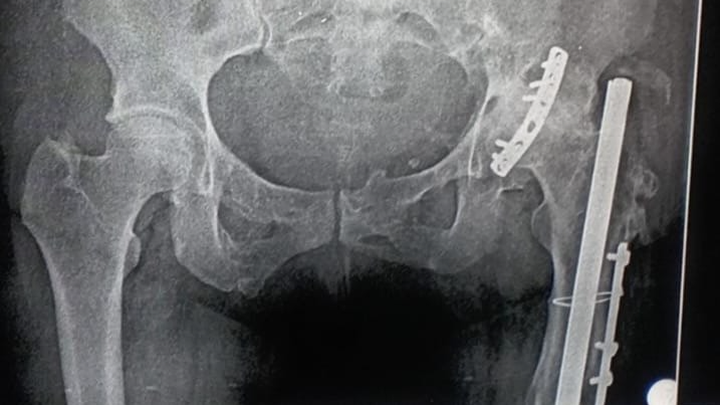

Hace algunos años, sufrí una fractura de cadera que fue tratada mediante la colocación de una placa de osteosíntesis. Con el paso del tiempo, la degeneración ósea ha avanzado y ahora los médicos indican que necesito un reemplazo de cadera. Este procedimiento consiste en la implantación de una prótesis de doble movilidad atornillada, con cabeza de cerámica, para asegurar una mayor estabilidad y durabilidad.